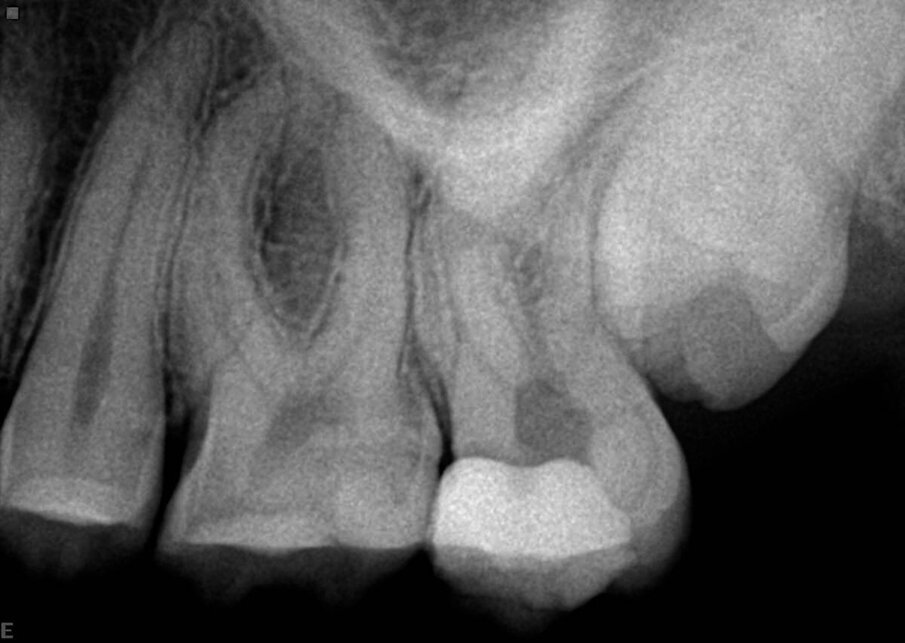

U ovom prvom primeru, pacijent je upućen na lečenje sinusnog trakta maksile (Sl. 1). Unutar fistule je postavljen konus od gutaperke, koji pokazuje put do mesta infekcije. Ovo je bio jednostavan slučaj, pripremljen korišćenjem Traverse turpije 25/0.08 u gornjem delu, nakon čega je nastavljen rad sa K-File 10 (Kerr) da bi se odredila radna dužina, a zatim je 40/0.06 Traverse file doveden do radne dužine. Naravno, tretman je podrazumevao kompletnu hemijsku pripremu i 3D obturaciju prostora kanala korena (Sl. 2).